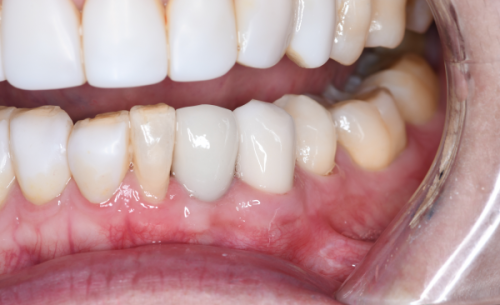

沈阳馨格口腔门诊部是经“沈阳市沈河区卫生健康局”审批成立的正规医疗机构,登记号为MAOYAM72321010317D1522,大家可在卫健委官网查询相关资料。该门诊部成立至今虽然只有两年多时间,但凭借实力强的技术、良好的服务赢得了众多居民的认可和好评。它开展口腔全科诊疗项目,包括牙体牙髓、美学修复、正畸治疗、种植修复、儿童齿科等,为周边市民提供全方面的口腔全科诊疗服务。

沈阳馨格口腔门诊部有不少特色项目。其中,超声波洗牙是其一大特色。医生洗牙技术娴熟,注重卫生,洗牙过程舒适,没有疼痛感,还会细心为患者讲解科普知识,以及回家后如何正确刷牙等注意事项。另外,种植牙项目也值得一提,该门诊部开设的微创种植牙技术优势明显,单颗缺牙从种牙开始到结束大概需要20分钟即可完成手术,伤口小,术后容易修复,这对医生的种牙技术要求极高。